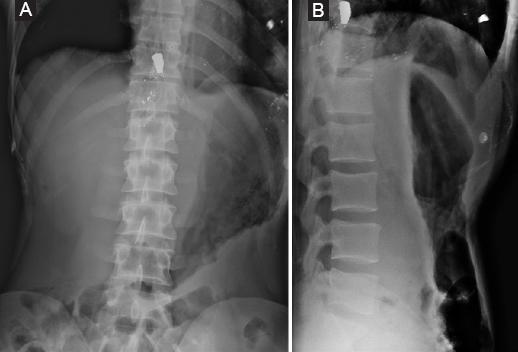

The approach to a patient with a spine injury secondary to a gunshot wound should always follow the ATLS (advanced trauma life support) protocol before managing any kind of spinal pathology in the trauma patient11. The initial radiologic evaluation should start with two plane radiographs (Fig. 1) even though many centers today advocate the minimal utility of radiographs and prefer using the computed tomography (CT) scan as the initial radiographic study (Fig. 2). CT scan with reconstruction should be considered in every gunshot injury to the spine to determine the integrity of the spine elements. In our center, we do not routinely request an MRI in gunshot spine injuries. The use of magnetic resonance imaging (MRI) in patients with gunshot injuries to the spine remains controversial. Dedini et al. reported that the use of MRI in a patient with retained projectile fragments requires knowing their composition; concluding that alloy and copper fragments are safe to continue the study, while steel is not12.

Figure 1 Lumbar AP and lateral radiograph. A: clinical images. B and C: an 29 y/o male patient with a gunshot injury in T11 (ASIA E).